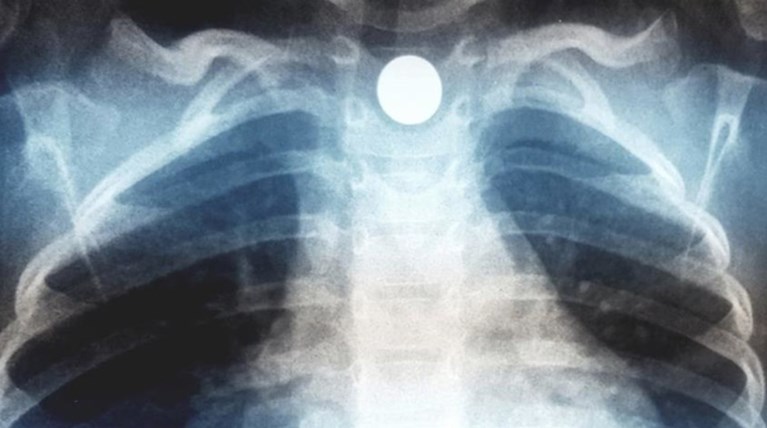

Στην ακτινογραφία που ανήρτησε ο γιατρός της οικογένειας, διακρίνεται το μαγνητάκι που σφήνωσε στον οισοφάγο του παιδιού. Για καλή του τύχη, το παιδάκι έλαβε έγκαιρα ιατρική φροντίδα και είναι καλά στην υγεία του.

Κατάποση ξένου σώματος (μαγνητάκι ψυγείου) από παιδάκι 2,5 ετών και ενσφήνωση του στον οισοφάγο. Στην ακτινογραφία το αντικείμενο απεικονίζεται ευκρινώς να παρεκτοπίζει και την τραχεία του παιδιού περαιτέρω προς τα δεξιά. Το μαγνητάκι είχε πέσει στο πάτωμα και το παιδί το "ανακάλυψε" και το κατάπιε ερήμην των γονέων. Η ενσφήνωση όλως ευνοϊκώς βοήθησε στην άμεση εκδήλωση συμπτωματολογίας από το ανώτερο πεπτικό και το αναπνευστικό. Το αντικείμενο αφαιρέθηκε ενδοσκοπικά και το παιδί βεβαίως είναι απολύτως καλά.